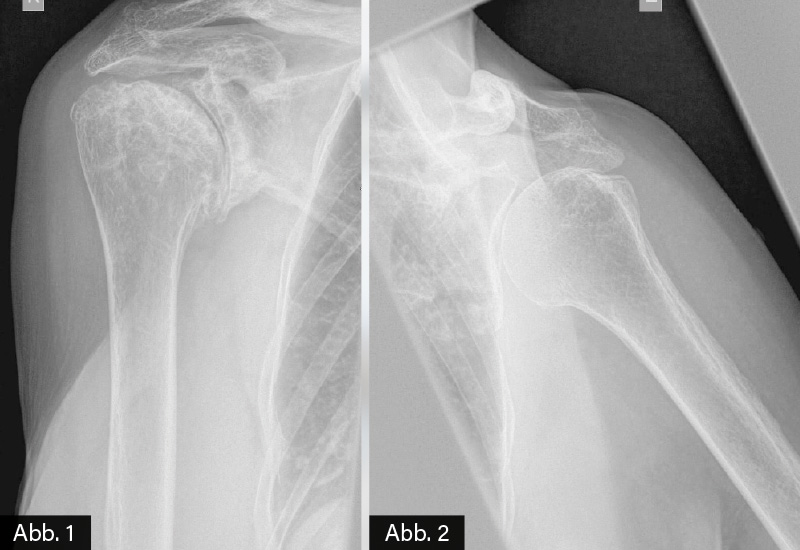

BILDGEBENDE DIAGNOSTIK: Röntgen (siehe Bild)

DIAGNOSE: Fortgeschrittene Omarthrose bds.

Zur Diagnostik werden Röntgenaufnahmen in zwei Ebenen angefertigt. Typische Befunde der Omarthrose sind eine Gelenkspaltverschmälerung, subchondrale Sklerosierung und in fortgeschrittenen Fällen osteophytäre Randanbauten und subchondrale Zystenbildung im Schulterpfannenbereich als auch dem betroffenen Humeruskopf. Bei klinischem V. a. eine Polymyalgia rheumatica (PMR) sollte auch aufgrund des Alters der Betroffenen eine Omarthrose ausgeschlossen werden. Im vorliegenden Fall waren die nicht erhöhten Entzündungsparameter (CRP, BKS), die für die PMR-Diagnose pathognomonischen Charakter besitzen, und das schlechte Ansprechen auf Steroide wichtige differenzialdiagnostische Hinweise, dass eine fortgeschrittene Omarthrose und nicht PMR Ursache der Schmerzsymptomatik war.